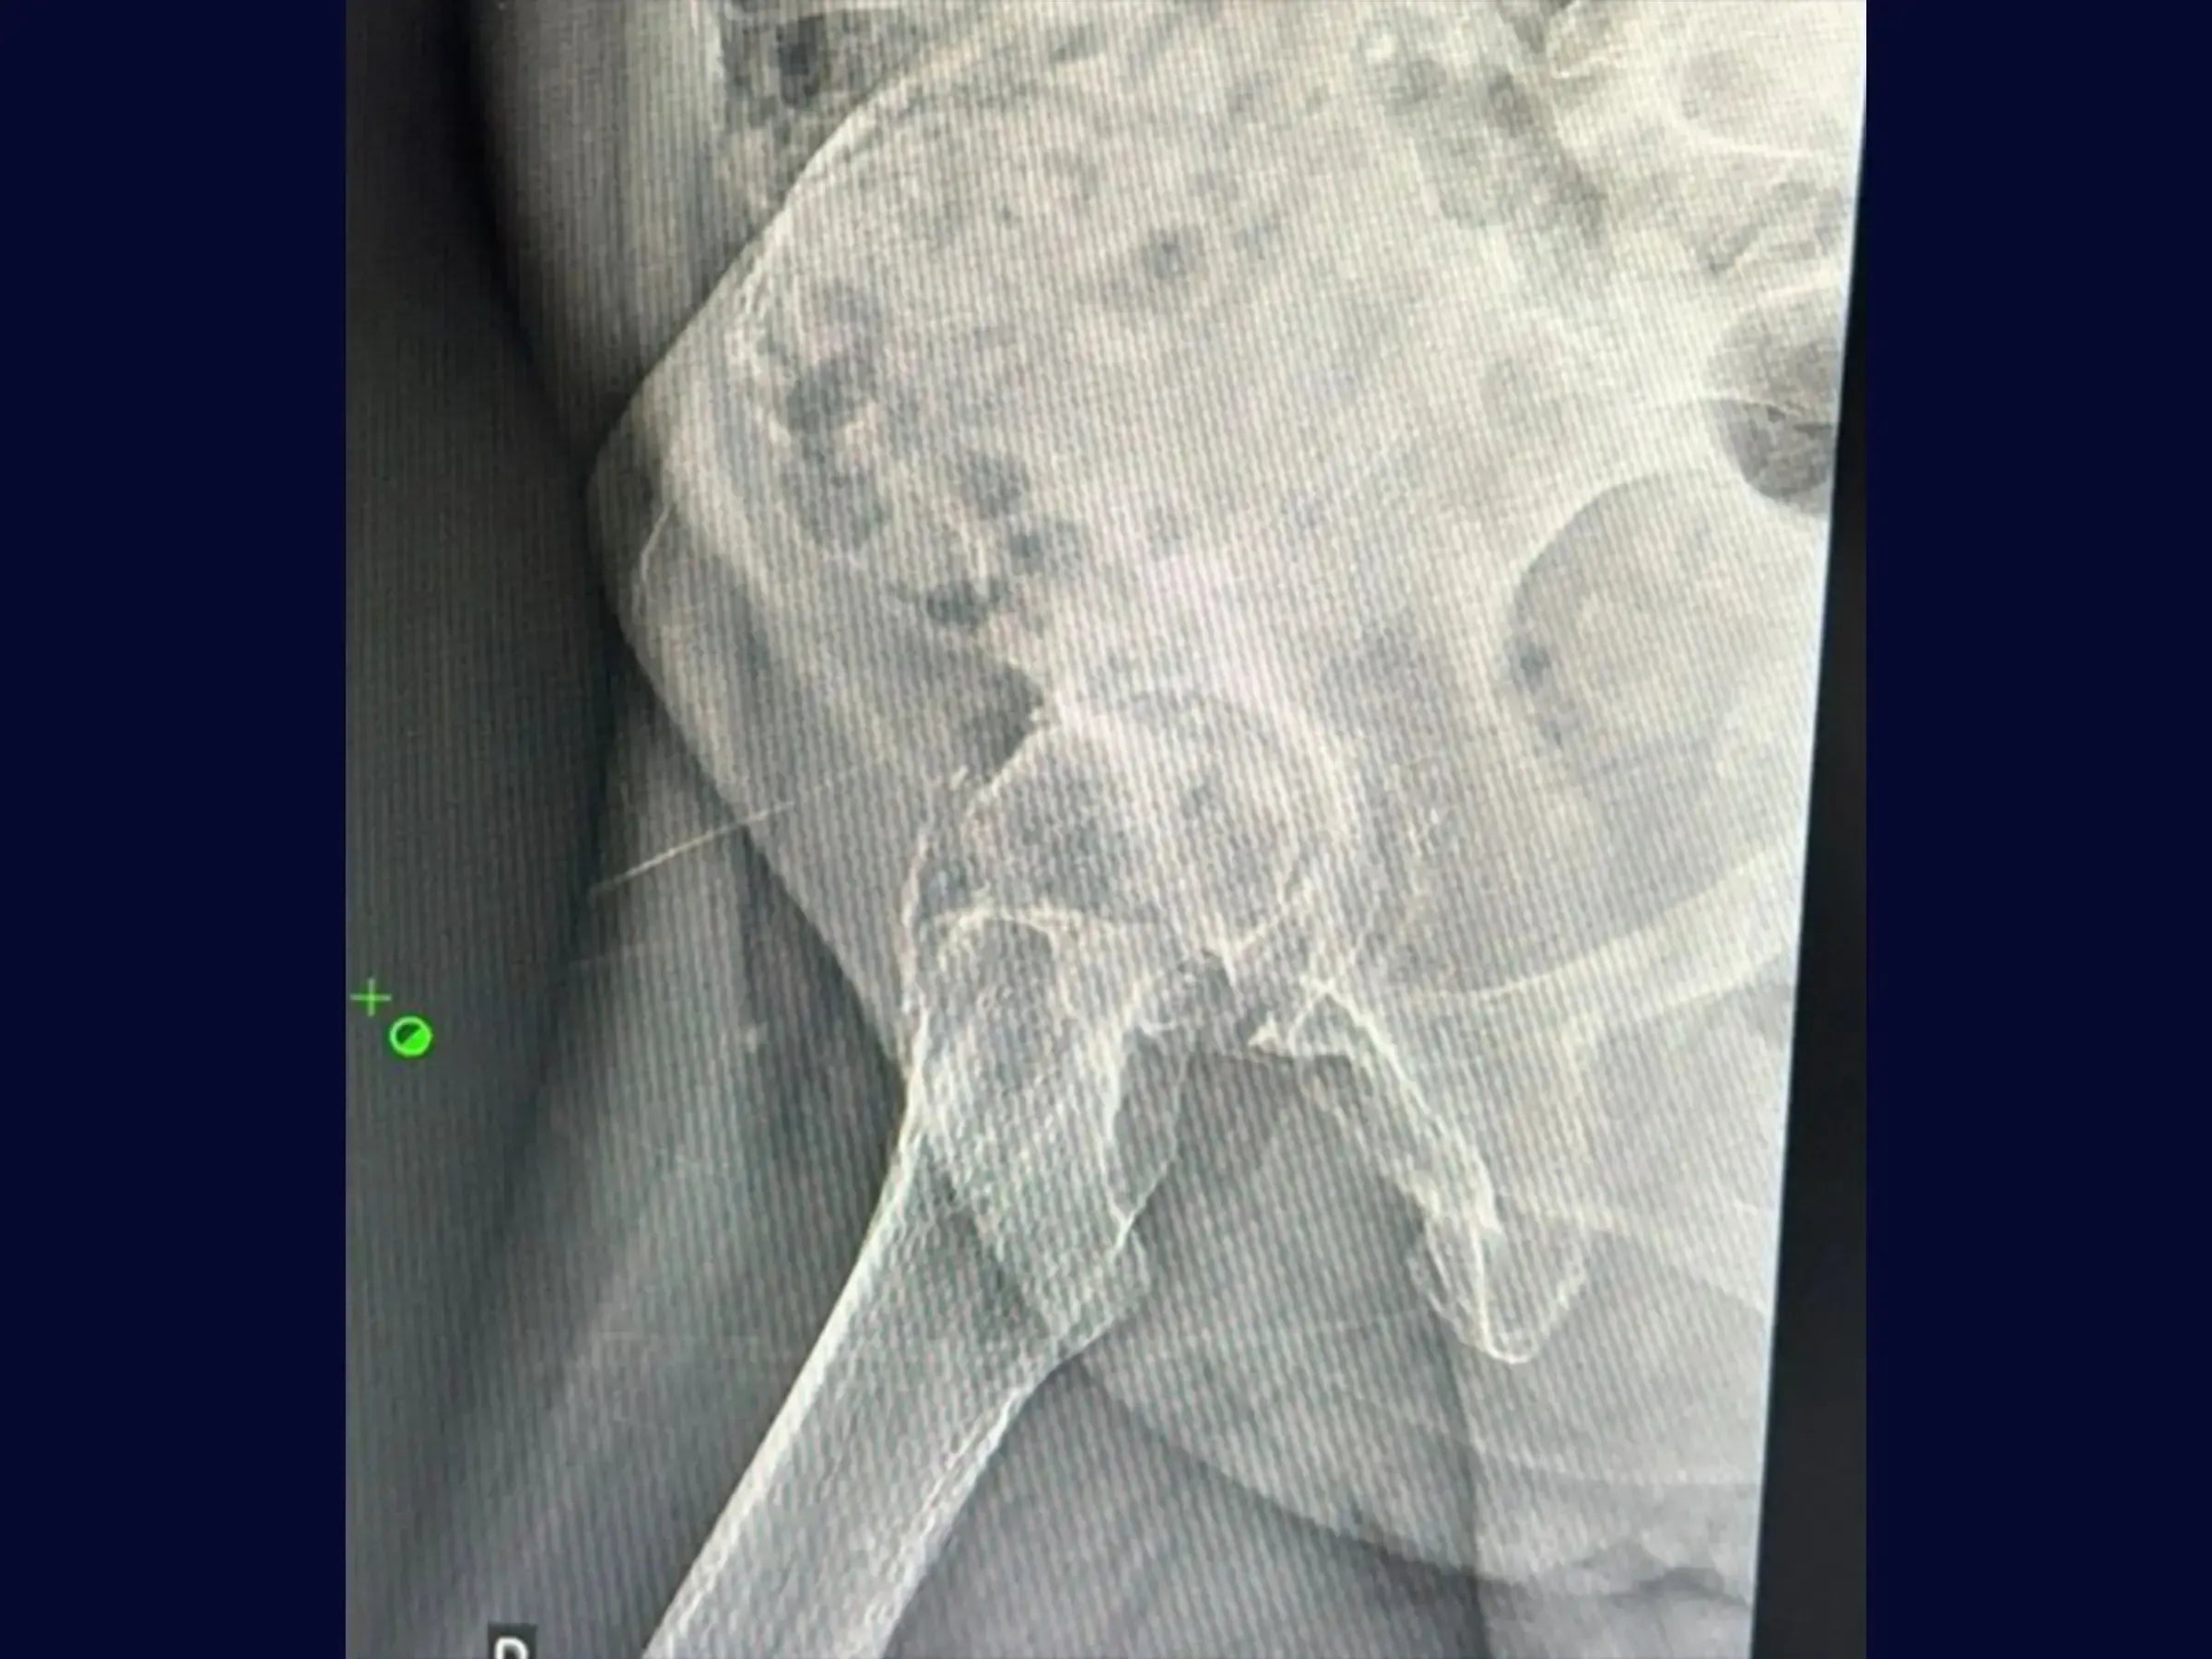

- Luxación segura y osteotomía precisa: abordaje sistemático de la luxación de cadera con retractor posicionado en el trocánter menor y demarcación de la osteotomía.